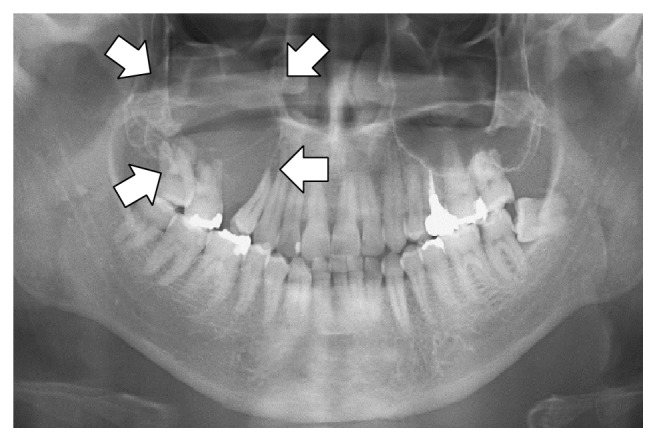

Набор данных для точной настройки зрения или мультимодальной модели также включает в себя ввод изображений. Например, в Llama 3.2 Vision Notebook используется рентгенографический кейс, чтобы показать, как искусственный интеллект может помочь медицинским работникам более эффективно анализировать рентгеновские снимки, компьютерную томографию и ультразвук.

Мы будем использовать выборочную версию набора данных рентгенографии ROCO. Вы можете получить доступ к набору данных здесь. Набор данных включает рентгеновские снимки, компьютерную томографию и ультразвуковое исследование, демонстрирующие медицинские условия и заболевания. К каждому изображению есть подпись, написанная экспертами с описанием. Цель состоит в том, чтобы точно настроить VLM, чтобы сделать его полезным инструментом анализа для медицинских работников.

| Image | Caption |

|---|---|

![]() |

Panoramic radiography shows an osteolytic lesion in the right posterior maxilla with resorption of the floor of the maxillary sinus (arrows). |